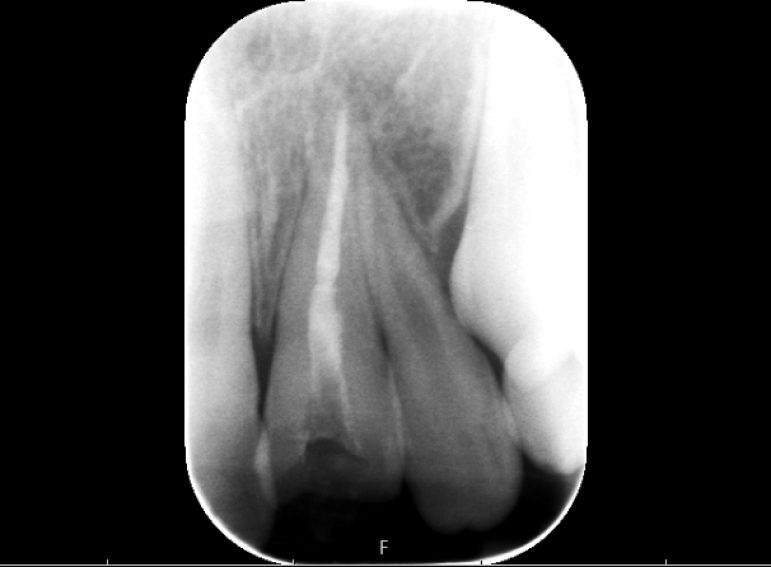

Surgical management of external cervical resorption.